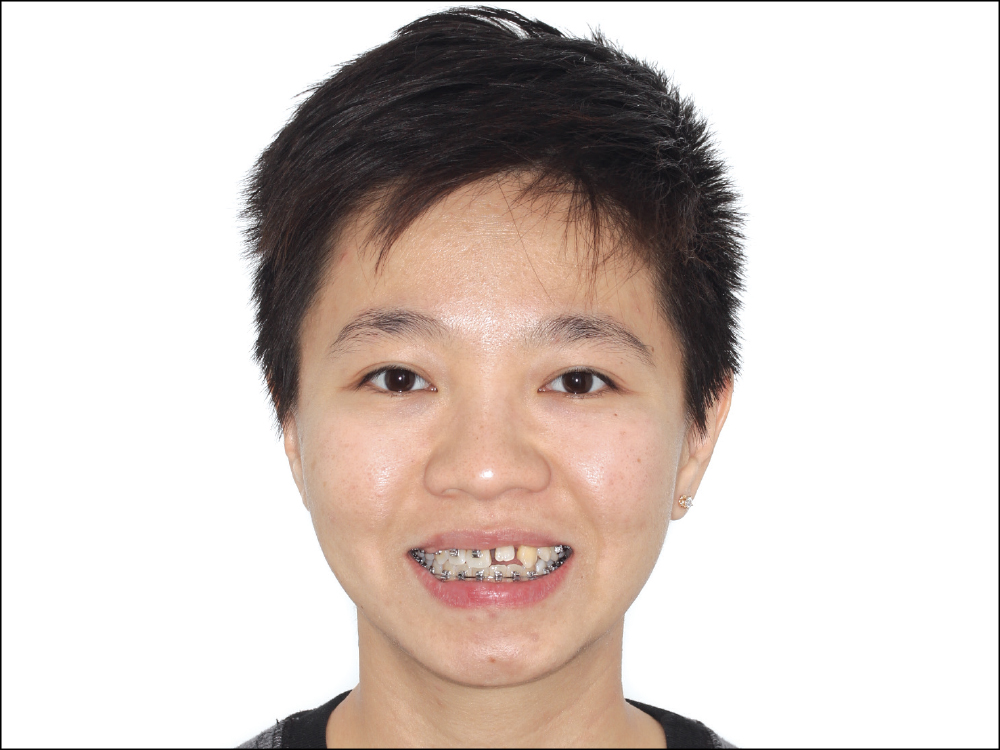

This patient originally presented to Dr. Ikeda, asking for improvement of her anterior esthetics. Tooth #9 was impacted and tooth #10 was blocked lingually. In addition, she had an anterior open bite and crowding in both arches, and her midline was off. She also presented with a negative anterior overjet and a unique end-to-end Class II posterior occlusion.

Figures 1a, 1b: The patient originally presented to Dr. Hideki Ikeda with an impacted tooth #9, which had caused all of her other upper teeth to suffer from misalignment and crowding.

The CBCT revealed a severely impacted upper left central with a very short and dilacerated root. The prognosis of the tooth was very poor, requiring extraction.